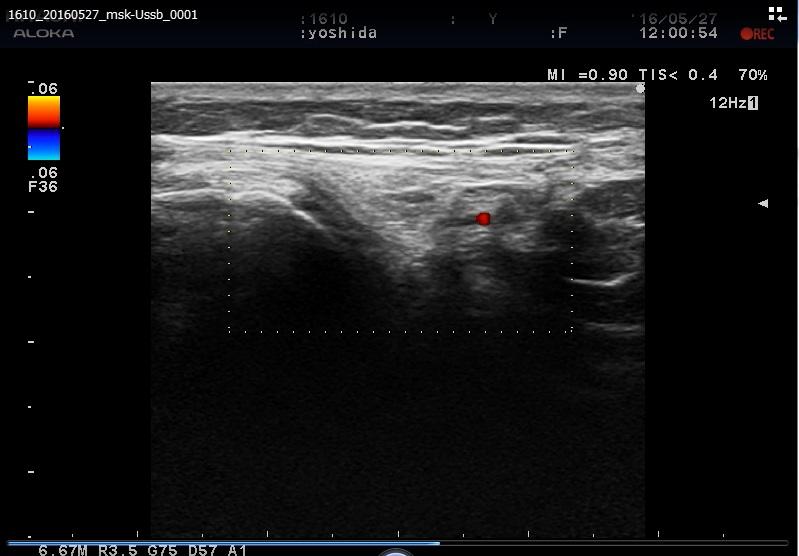

アイスホッケー ゴールキーパーで他人に膝の上に乗られ「膝の半月板」痛められた方。

lateral collateral ligament2.jpglateral collateral ligament.JPG